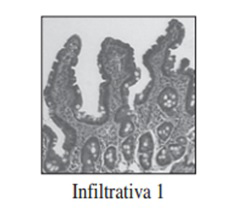

Imágenes tomadas durante la endoscopia digestiva alta y la colonoscopia. Se aprecia una mucosa de aspecto y vascularización normal, sin lesiones visibles. Se progresa con el colonoscopio hasta el íleon. Todo resulta macroscópicamente normal. Se toman biopsias de todos los segmentos explorados.

La endoscopia es el método de elección para el diagnóstico y seguimiento de la EII. Permite una visión macroscópica de la mucosa intestinal y la toma de múltiples biopsias para el estudio histológico.

Realizamos una endoscopia digestiva alta y una colonoscopia a la paciente con toma de biopsias, obteniendo el informe de Anatomía patológica.